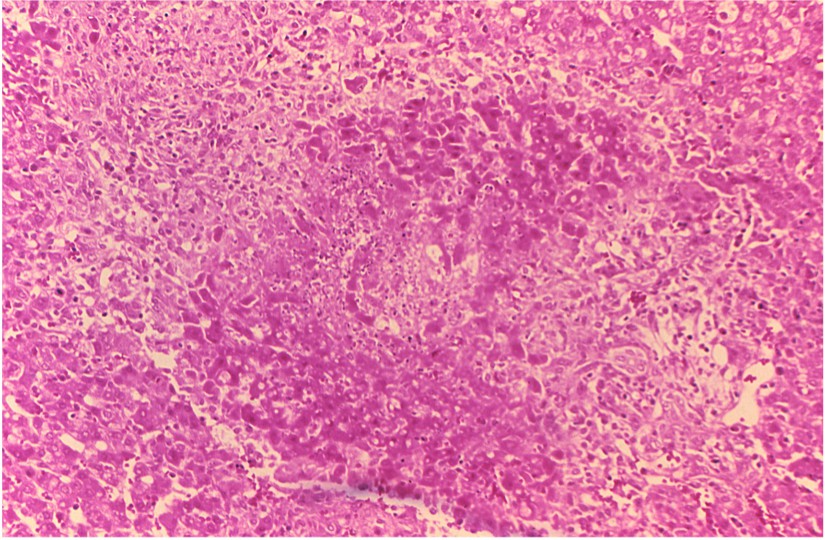

Granuloma and necrosis in the liver of a guinea pig infected with Brucella suis.Fig.1 Granuloma and necrosis in the liver of a guinea pig infected with Brucella suis.